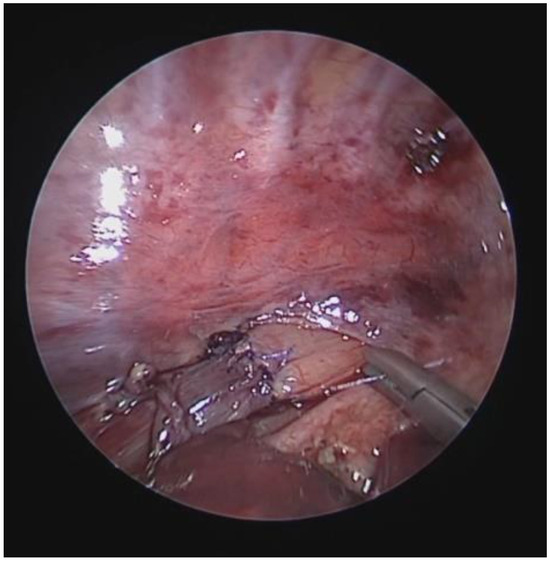

Diagnosis, Treatment, and Follow-Up of Tracheo/Bronchomalacia in Children: The Italian Multicenter Experience

by Angelo Florio, Michele Ghezzi, Francesca Rizzo, Paolo Del Greco, Katia Perri, Fabio Antonelli, Annalisa Gallizia, Francesco Santoro, Elena Ribera, Francesco Macchini, Michele Torre, Francesco Donati, Federica Lena, Vittorio Guerriero, Paola Borgia, Valerio Gentilino, Roberto D’Agostino, Federica Porcaro, Alessio Conte, Duino Meucci, Roberto Baggi, Michele Gaffuri, Pietro Salvati and Oliviero Saccoadd Show full author list remove Hide full author list

Children 2025, 12(11), 1511; https://doi.org/10.3390/children12111511 - 7 Nov 2025

Background: In pediatric age, the central airways are more flexible and mobile, with tracheal and bronchial walls easily tending to collapse, allowing partial or complete occlusion of the lumen: a situation described as tracheobronchomalacia (TBM). This is a condition that causes an increase [...] Read more.

Background: In pediatric age, the central airways are more flexible and mobile, with tracheal and bronchial walls easily tending to collapse, allowing partial or complete occlusion of the lumen: a situation described as tracheobronchomalacia (TBM). This is a condition that causes an increase in intrathoracic pressure that may accentuate airway collapse, and a biphasic or barking cough appears. Objectives: Although TBM is relatively frequent in pediatric age, the diagnostic criteria and subsequent treatment do not follow well-standardized criteria and often vary from pediatric center to center. Therefore, there is a need to standardize diagnostic procedures and the resulting medical or surgical treatments. Methods: We therefore organized a day of meetings to talk about TBM, inviting all Italian pediatricians and pediatric surgeons who diagnose and treat patients with this pathology on a daily basis. Results: This work, collecting all the meeting interventions, is a compendium that deals with all aspects of TBM, emphasizing the most correct criteria to diagnose and therefore best treat each pediatric patient with this clinical condition. We give particular emphasis to the need to perform static and dynamic videobronchoscopy (S/DVBS) to verify the patency of the tracheal lumen, so as to evaluate the severity of TBM. Conclusions: this work deals with TBM in all its diagnostic and treatment aspects and can be a valid help for all pediatricians who treat these patients. Full article

Show Figures

Figure 1